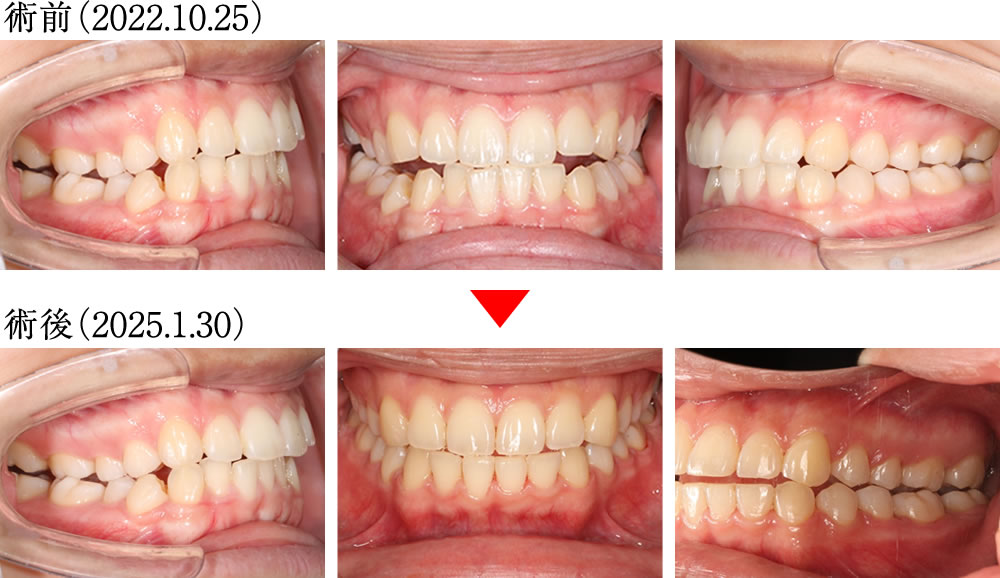

術前は上下顎の正中がずれており、右側に咬合不良が見られる歯並びでした。しかし術後は上下の正中がしっかりと揃い、理想的な被蓋関係で噛める、きれいで安定した歯並びへと改善しました。